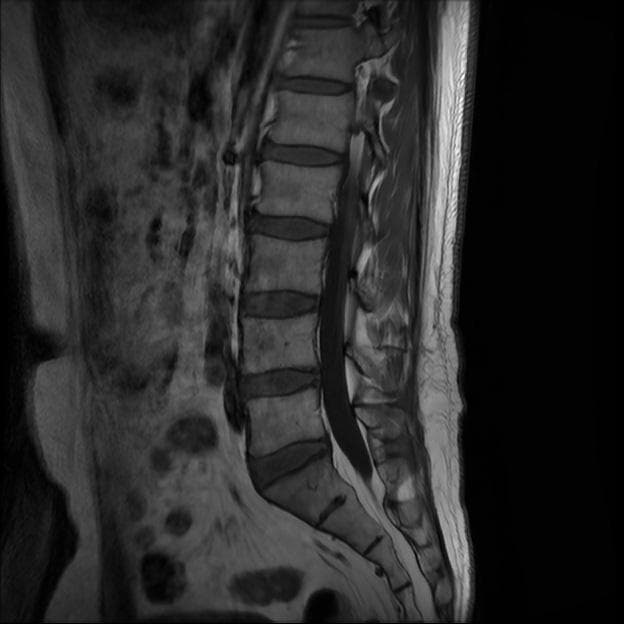

이번에 허리 MRI찍었는데

상태 어떤지 고견 여쭙습니다.

큰 이상이나 문제점은 없어 보이는 것으로 생각되는데요, 허리통증이 지속되는 경우에는 반드시 디스크 질환에 의한것은 아닐 수 있습니다.

현재로썬 디스크 상태는 심하지않는것으로 확인이 됩니다.

MRI 영상 커트로 판독을 할 수는 없습니다.